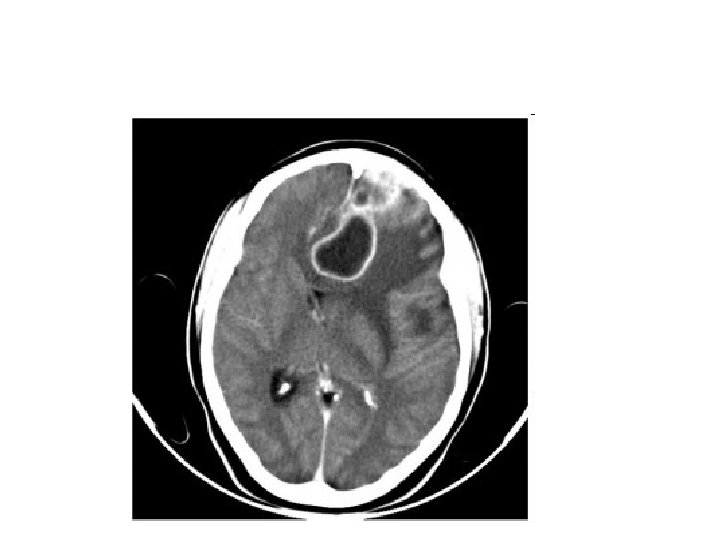

DIAGNOSIS • The diagnosis is established by a computed tomography (CT) (with contrast) examination. • At the initial phase of the inflammation (which is referred to as cerebritis), the immature lesion does not have a capsule and it may be difficult to distinguish it from other space-occupying lesions or infarcts of the brain. • Within 4– 5 days the inflammation & dead brain tissue are surrounded with a capsule, which gives the lesion the famous ring-enhancing lesion appearance on CT examination with contrast (since intravenously applied contrast material can not pass through the capsule, it is collected around the lesion and looks as a ring surrounding the relatively dark lesion).

DIAGNOSIS • Ring enhancement may also be observed in cerebral hemorrhages and some brain tumors. • However, in the presence of the – – rapidly progressive course with fever, focal neurologic findings (hemiparesis, aphasia) & signs of increased intracranial pressure, the most likely diagnosis should be the brain abscess.